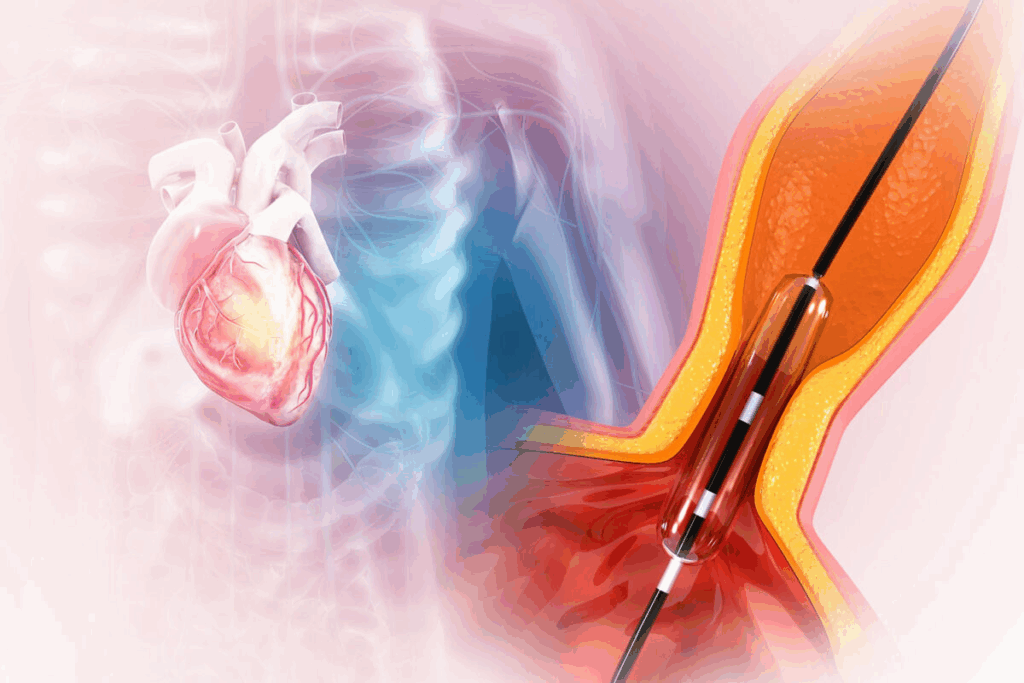

RFA targets and stops pain nerves. A doctor uses X-rays to guide a needle to the nerves. Then, radio waves heat up the nerve, stopping it from sending pain signals.

RFA is precise because it targets specific nerves for pain. This is done with advanced imaging like fluoroscopy or ultrasound. This precision helps avoid harming other tissues.

During Radiofrequency Ablation

During RFA, you’ll lie on your stomach on an X-ray table. The procedure is done under local anesthesia to keep you comfortable. Here’s what happens:

- Your skin is cleaned and made ready.

- A local anesthetic is given to numb the area.

- A needle is placed near the nerve causing pain, guided by X-ray.

- An electrode is put through the needle.

- Radiofrequency energy heats the nerve, stopping it from sending pain signals.